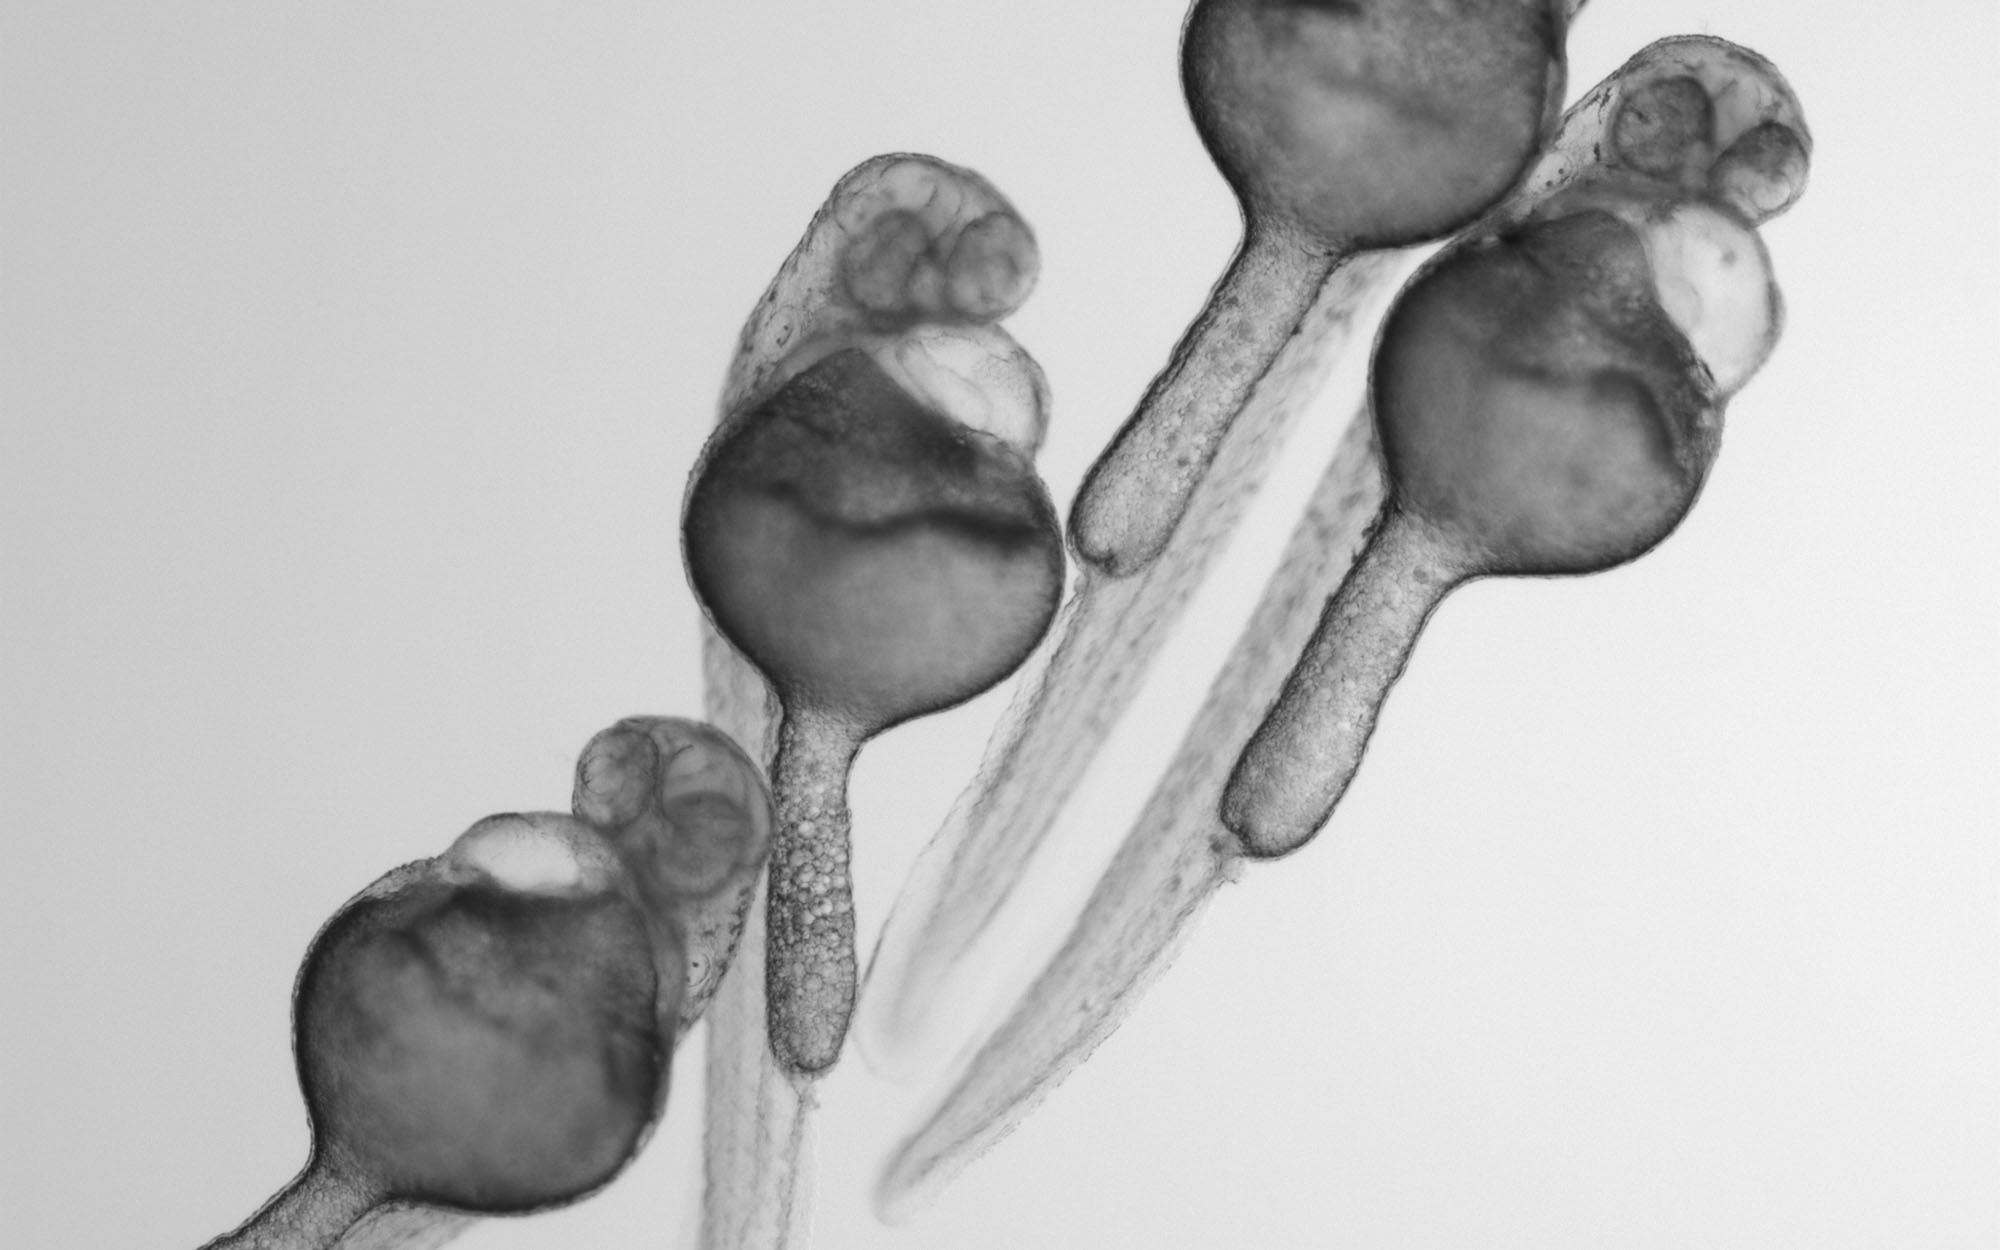

Much is known about genes that are required for normal embryonic development, but how chemicals in the environment influence these genes to cause congenital anomalies (also called birth defects) is less well understood. An estimated 6% of babies worldwide are born with a congenital anomaly (World Health Organization). Using genetic and pharmacologic approaches, we study how prescription drugs cause congenital anomalies at the molecular and cellular levels. We hope that our studies will make prescription drugs safer for pregnant women and reveal new and fundamental insights into human embryonic development.